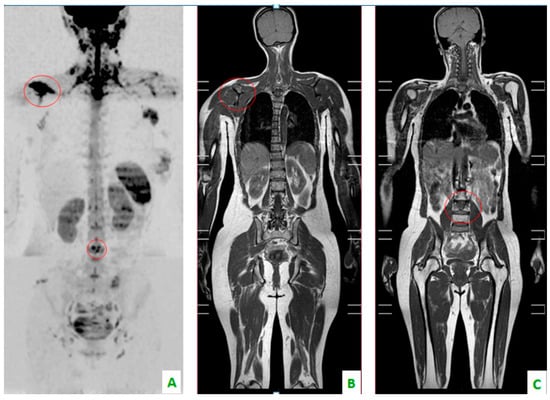

Figure 1. (A) Diffusion-weighted imaging (DWI) sequence in sagittal plane shows focal alteration of diffusivity. (B) The sagittal plane of TSE T1 shows, in the same level, a hypointense region of the dorsal soma related to the secondary localization of prostate cancer.